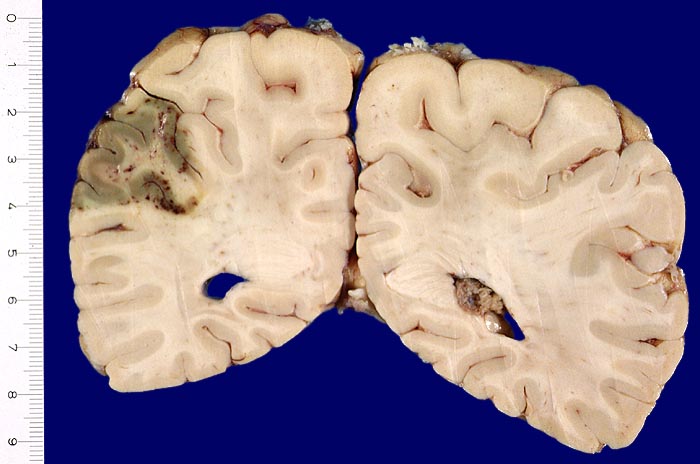

Frischere anämische Enzephalomalazie mit sekundären Einblutungen

Frische Enzephalomalazie occipito-parietal links (8x3x3cm) im peripheren Versorgungsgebiet der A. cerebri media links. Grauverfärbung der Hirnrinde im Infarktareal und punktförmige dunkelrote Einblutungen.

Rezidivierter Myokardinfarkt mit Fibrinthrombus in der linken Herzkammer und Morbus embolicus.